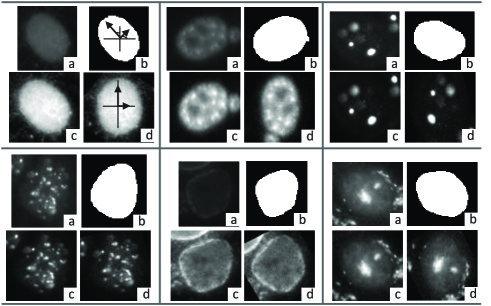

The brightness and contrast of the HEp- cell images provided by the ICPR 2014 contest (ICPR2014 dataset in short) vary greatly. To reduce this variance and enhance the contrast, we normalize each image by first subtracting the minimum intensity value of the image. The resulting intensity is then divided by the difference between the maximum and minimum intensity values. Furthermore, each image is resized to to guarantee a uniform scale of all the images used for training. This size is approximately the average size of all the cell images. Examples of six staining patterns in ICPR2014 dataset and the preprocessed images are shown in Fig. 2. In addition, we just use the preprocessed whole cell images to train our network instead of adopting a mask to only keep the foreground within each cell as Malon et al. in (Foggia and Vento, 2013), because the mask information of each cell is usually unavailable in practice, and we find that the classification performance of our system is adversely affected by using cell masks.

To demonstrate the second point, we pre-align each cell image to approximately have the same global orientation. In this way, if the global orientation variance is really the main factor affecting the training performance of the CNN, we shall observe some improvement by using the pre-aligned training set. Also, augmenting this pre-aligned training set with rotated images shall not lead to significantly better classification performance.

To investigate our hypothesis, we apply principal component analysis (PCA) to each cell’s mask to obtain the principal direction of its shape. Each contrast normalized cell is rotated to make this principal direction to be vertical and then is resized. Applying this process to all training cell images makes them pre-aligned. These operations are illustrated in the upper left portion (as indicated) in Fig.2, followed by more examples of cell images before and after alignment. After that, we use the pre-aligned training images to train the CNN and then classify test images which are also pre-aligned.